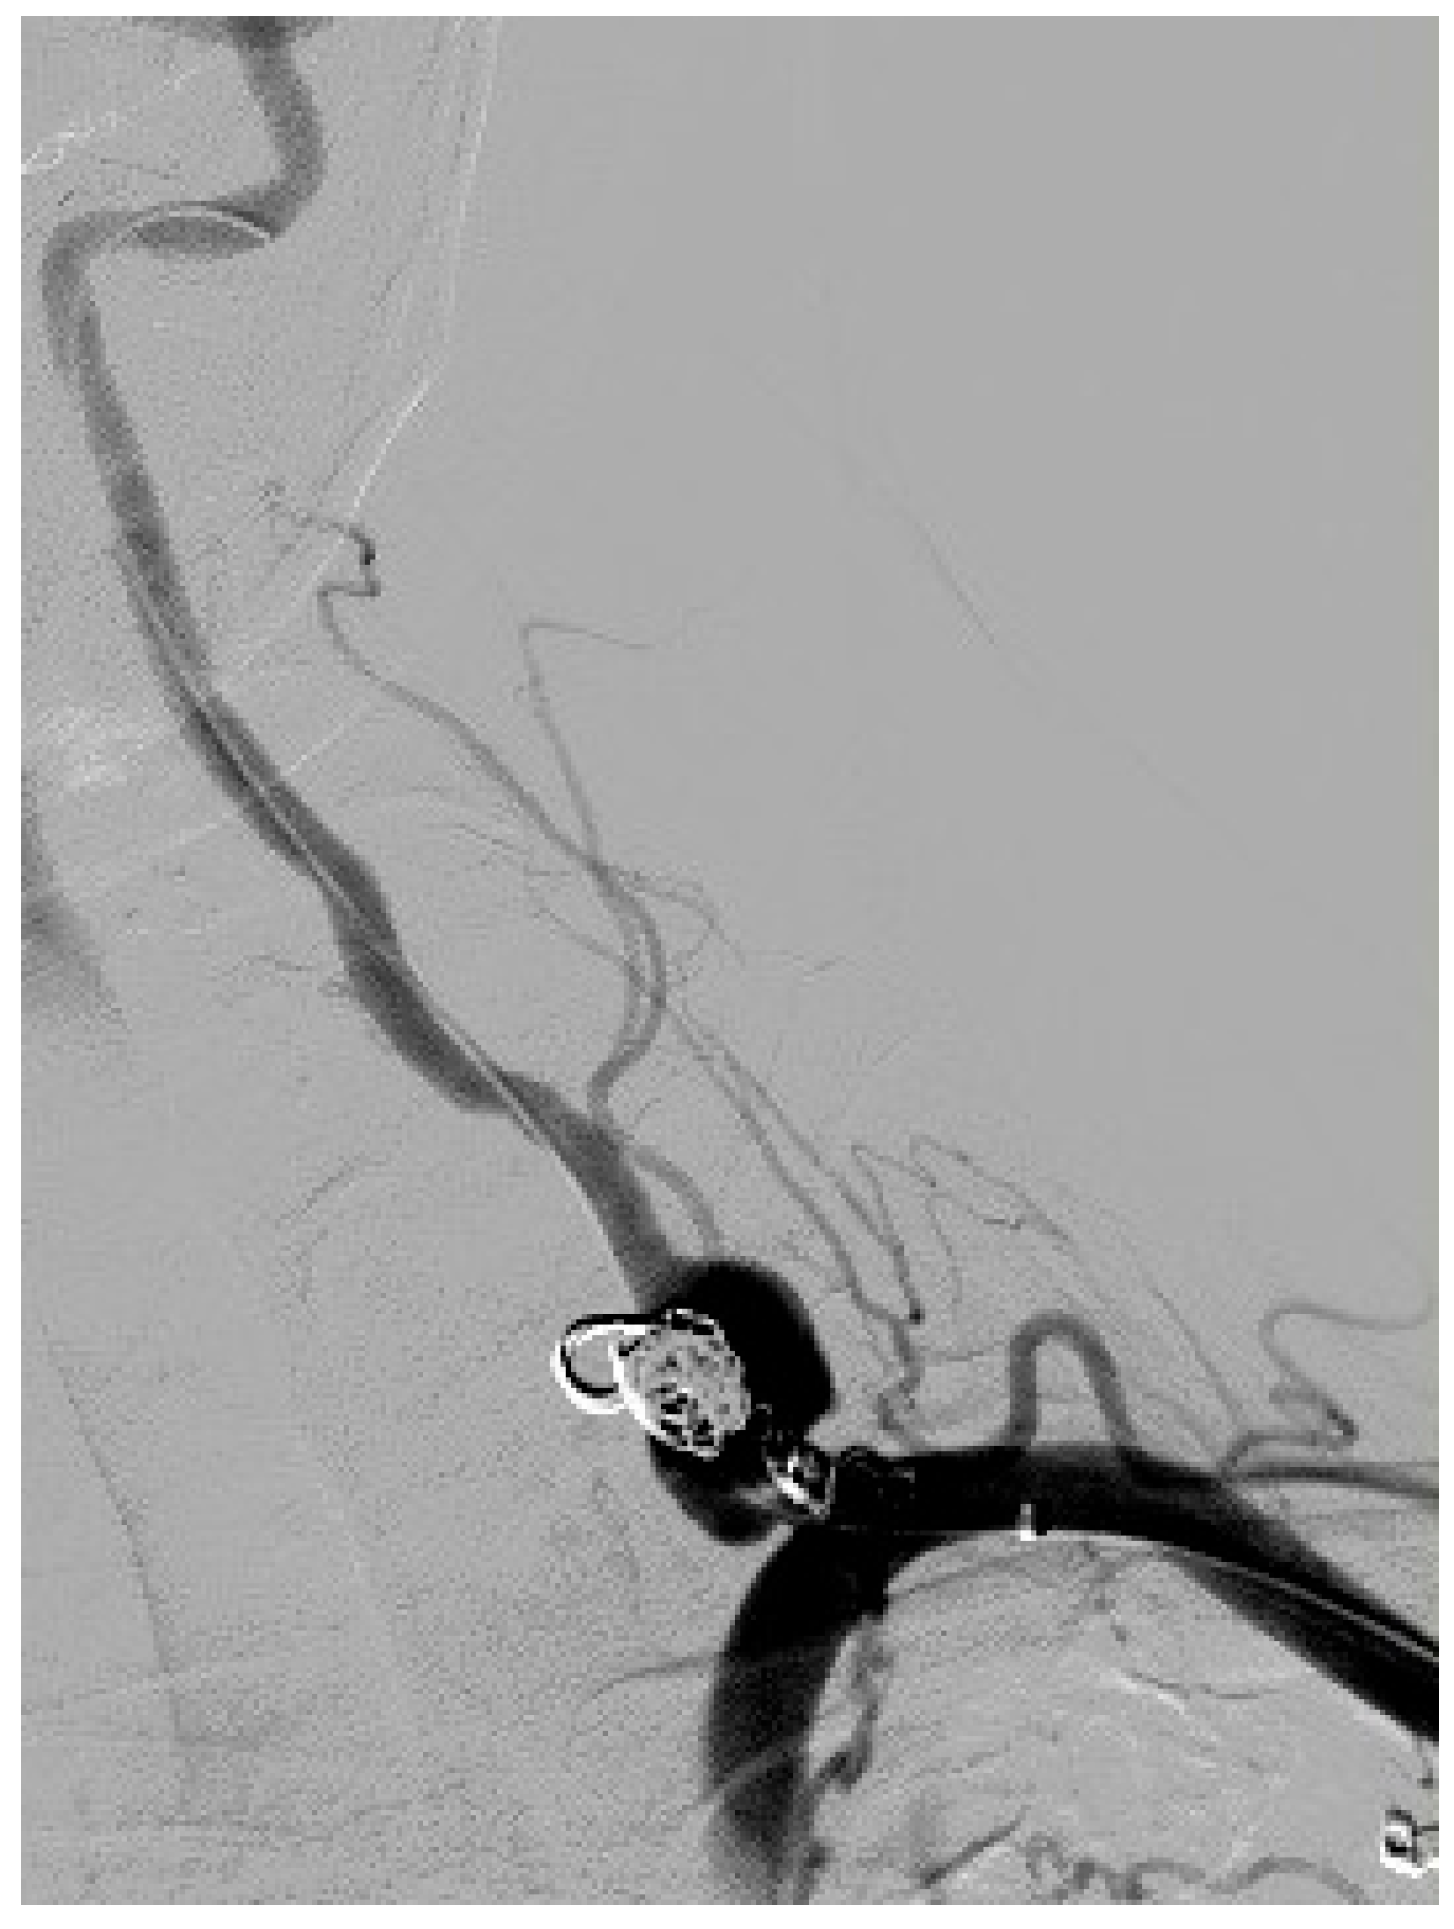

2. Case Presentation

| 3 days after CS | Centre for Vascular Surgery | emergency endovascular coiling intervention |

| 2 months after CS | Admission to Centre for Vascular Surgery | Left sided endovascular treatment (ET) of the ipsilateral VAA |

| 2 days after ET | Discharge from Centre for Vascular Surgery | Monitoring and dual antiplatelet therapy |